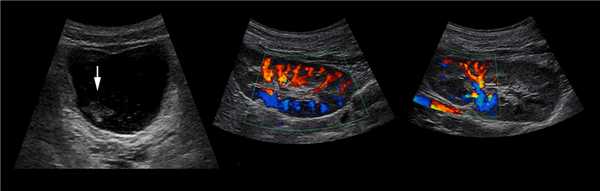

Рисунок. Уретероцеле (стрелка) на УЗИ и КТ.

Рисунок. Дистальный отдел мочеточника расширен, в мочевом пузыре анэхогенное образование с тонким и ровным контуром — уретероцеле.

Рисунок. Двустороннее уретероцеле на УЗИ: в режиме ЦДК из верхушек уретероцеле определяется выброс мочи.